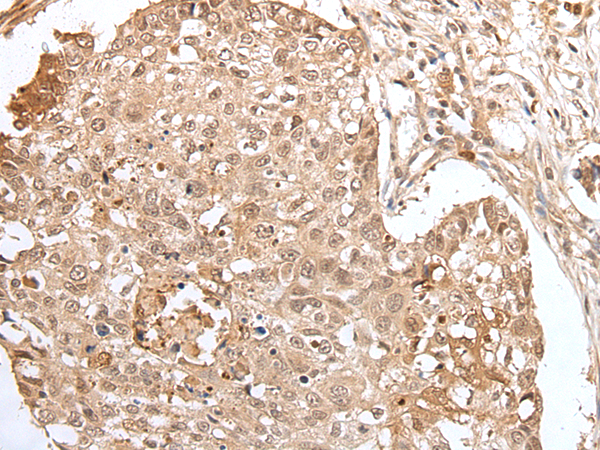

分类: 科研抗体货号: P05809别名: MCT6; MCT7应用: WB,IHC反应种属: Human